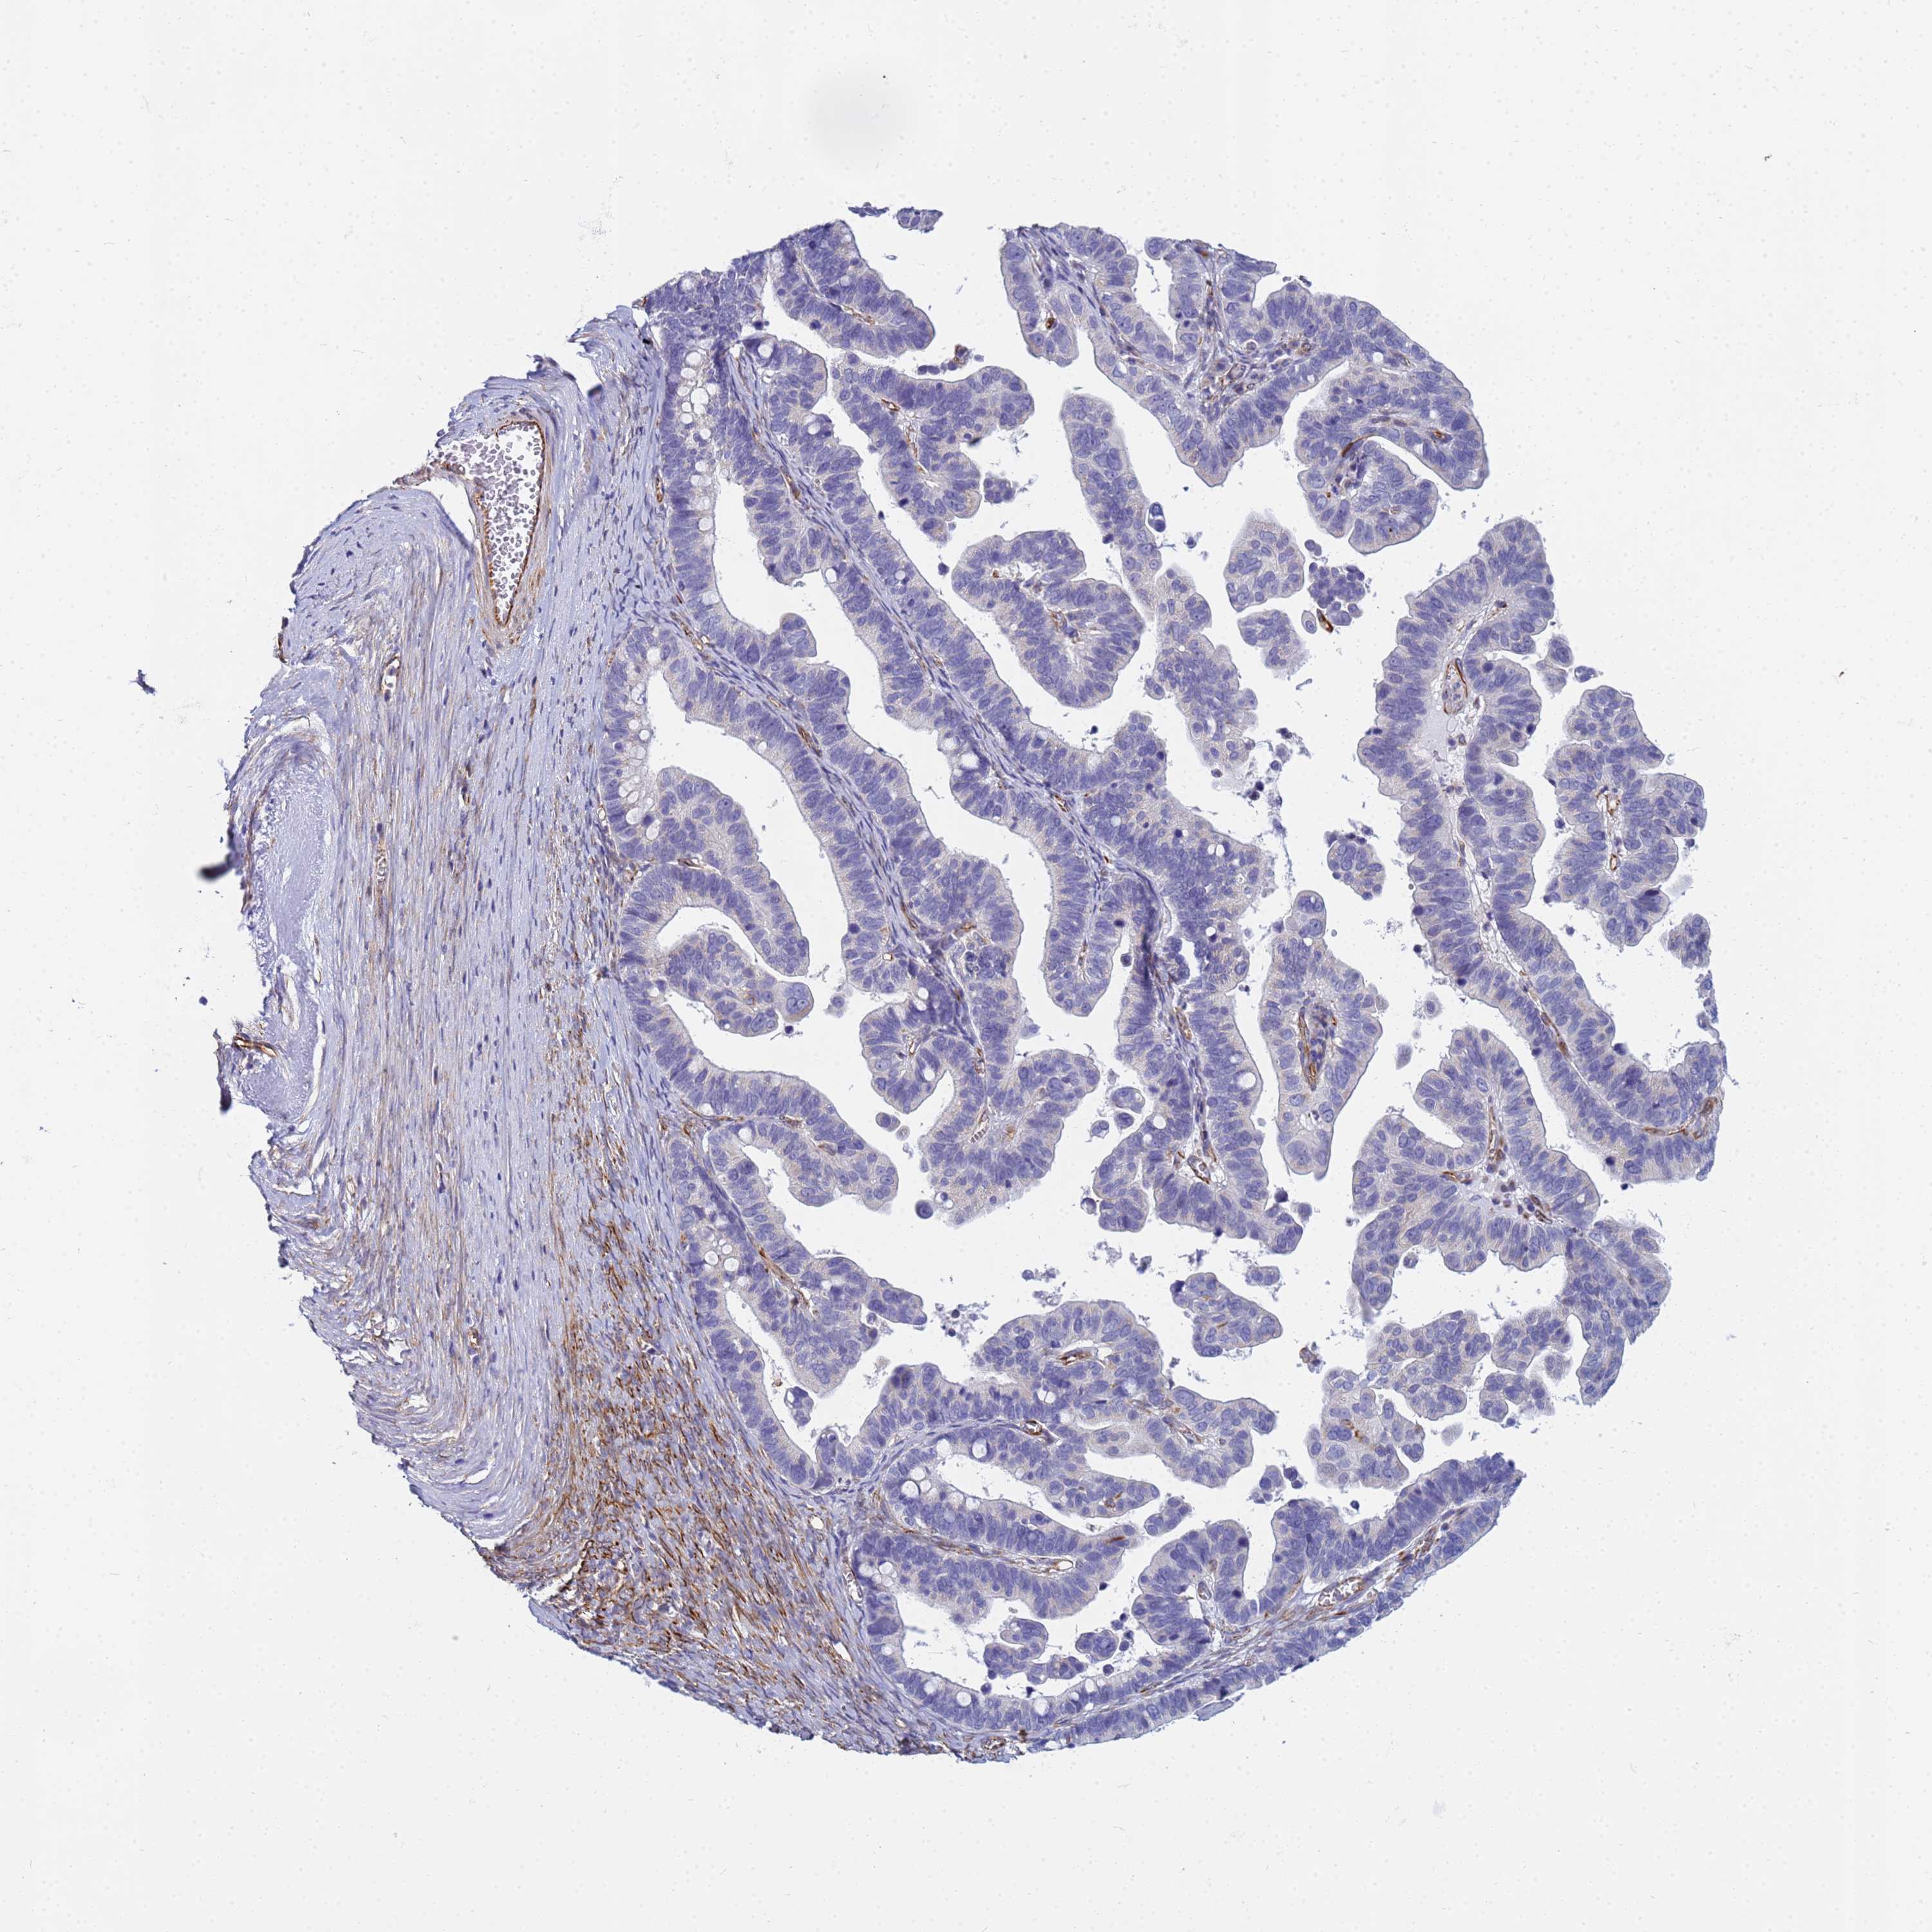

OVARIAN CANCER - Protein expressioni

A mouse-over function shows sample information and annotation data. Click on an image to view it in a full screen mode. Samples can be filtered based on level of antibody staining by selecting one or several of the following categories: high, medium, low and not detected. The assay and annotation is described here.

Note that samples used for immunohistochemistry by the Human Protein Atlas do not correspond to samples in the TCGA dataset.

Antibody stainingi

Antibody staining in the annotated cell types in the current human tissue is reported as not detected, low, medium, or high, based on conventional immunohistochemistry profiling in selected tissues. This score is based on the combination of the staining intensity and fraction of stained cells.

Each image is clickable and will lead to virtual microscopy that enables deeper exploration of all samples and also displays staining intensity scores, fraction scores and subcellular localization as well as patient and tissue information for each sample.

Antibody HPA045278

Staining

High

Medium

Low

Not detected

Intensity

Strong

Moderate

Weak

Negative

Quantity

>75%

75%-25%

<25%

None

Location

Nuclear

Cytoplasmic/membranous

Cytoplasmic/membranous,nuclear

Cystadenocarcinoma, serous, NOS

Carcinoma, endometroid

Cystadenocarcinoma, mucinous, NOS

Carcinoma, NOS